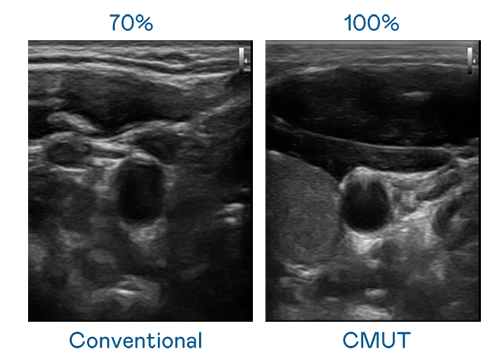

CMUT жҠҖжңҜжҳҜдёҖз§Қз”Ёз”өе®№ејҸеҫ®жңәз”өе…ғ件жқҘдә§з”ҹи¶…йҹіжіўи®ҜеҸ·зҡ„жҠҖжңҜгҖӮдёҺдј з»ҹ PZT еҺӢз”өејҸжҠҖжңҜзӣёжҜ”пјҢCMUT йў‘е®ҪеўһеҠ 30%пјҢжӣҙе®Ҫйў‘зҡ„и¶…йҹіжіўи®ҜеҸ·и®©еҪұеғҸи§ЈжһҗеәҰеӨ§е№…жҸҗеҚҮпјҢжҳҜе®һзҺ°й«ҳеҪұеғҸе“ҒиҙЁеҢ»з–—и¶…йҹіжіўжү«жҸҸгҖҒдҝғиҝӣзІҫеҮҶеҢ»з–—еҸ‘еұ•зҡ„е…ій”®жҠҖжңҜгҖӮ

еӨ§йў‘е®ҪеёҰжқҘи¶…жё…жҷ°еҪұеғҸ

и¶…йҹіжіўеҪұеғҸзҡ„и§ЈжһҗеәҰй«ҳдҪҺпјҢйҰ–е…ҲеҸ–еҶідәҺжҺўеӨҙиғҪеҸ‘еҮәзҡ„и®ҜеҸ·йў‘е®ҪгҖӮAGзҷҫ家д№җ CMUT еҸҜжҸҗдҫӣй«ҳжё…жҷ°зҡ„и¶…йҹіжіўи®ҜеҸ·пјҢжҸҗдҫӣй«ҳйў‘е®ҪгҖҒй«ҳзҒөж•ҸеәҰгҖҒеҪұеғҸзә№зҗҶз»ҶиҠӮжӣҙй«ҳзҡ„и¶…йҹіжіўеҪұеғҸпјҢеҚҸеҠ©еҢ»жҠӨдәәе‘ҳзј©зҹӯеҪұеғҸеҲӨиҜ»ж—¶й—ҙеҸҠеҲ©з”ЁзІҫеҮҶзҡ„еҢ»з–—еҪұеғҸиҝӣиЎҢиҜҠж–ӯгҖӮ